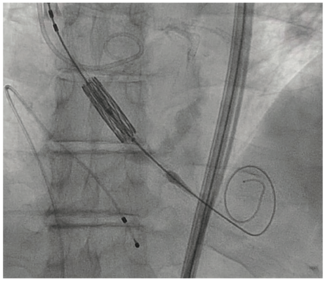

We report a case of a 77-year-old Caucasian male who underwent transcatheter aortic valve replacement (TAVR) with the rare complication of valve embolization into the ascending aorta. The patient underwent evaluation for TAVR after reporting...